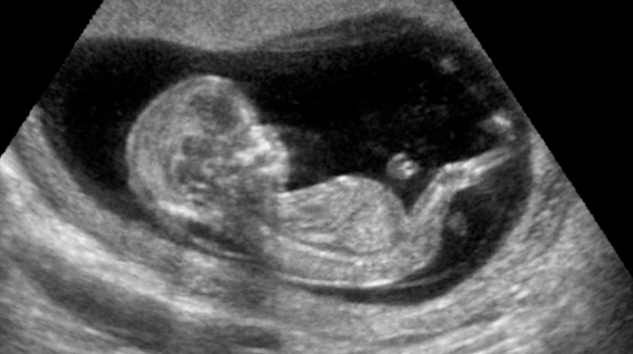

Un reciente estudio realizado por investigadores en México ha revelado que la música clásica puede ayudar a estabilizar la frecuencia cardíaca fetal, lo que podría tener beneficios en su desarrollo neurológico.

Los expertos de la Universidad Autónoma del Estado de México, la Universidad Autónoma Metropolitana, el Hospital General Nicolás San Juan y el Instituto Nacional de Cardiología Ignacio Chávez estudiaron cómo estas melodías afectaban la variabilidad de la frecuencia cardíaca fetal, un indicador clave del desarrollo del sistema nervioso autónomo.